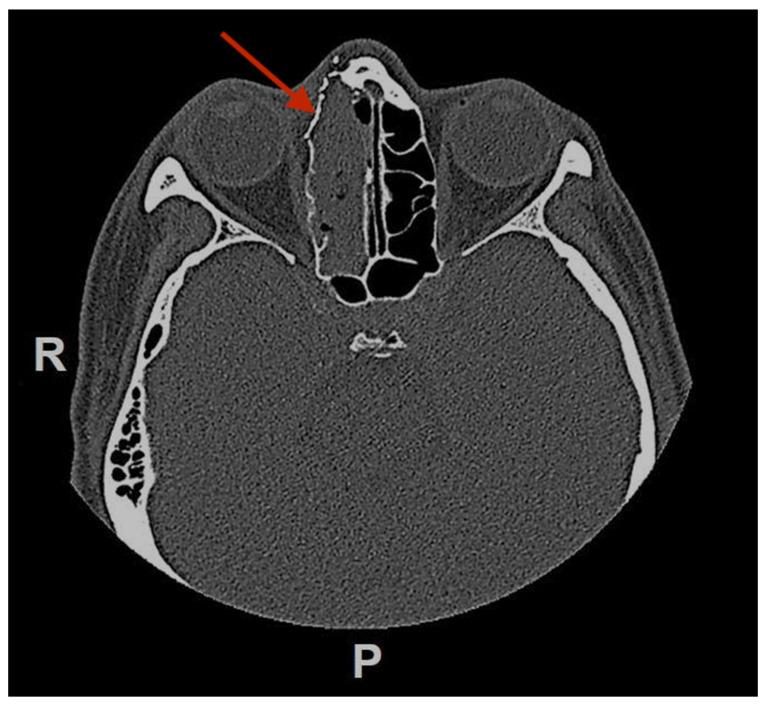

Glomangiopericytomas are a rare type of sinonasal tumors with high relapse rates. Endoscopic sinus surgery is the classical technique to remove such tumors. Here we report a case of sinonasal glomangiopericytoma with orbital extension, infrequently described in the literature. A 50 year-old woman was referred to our hospital because of a right paranasal painless swelling, which appeared 9 months ago and was slowly increasing in size since her first visit. A Magnetic Resonance Imaging (MRI) revealed a tumor (18 × 25 × 37 mm) centered on the right ethmoidal cells, with adjacent nasal bone erosion and a right orbital invasion. The tumor was removed with a combined surgical approach (endoscopic and trans-sinusal frontal approach) after pre-surgical embolization. Based on the results of the histopathological examination, the diagnosis of a glomangiopericytoma was confirmed. The patient was discharged after one week, and an uneventful long-term follow-up.

摘要

血管外皮细胞瘤是一种罕见的鼻窦肿瘤,复发率高。鼻内镜鼻窦手术是切除此类肿瘤的经典技术。在此,我们报告一例鼻窦血管外皮细胞瘤侵犯眼眶的病例,该病例在文献中鲜有描述。一名50岁女性因右侧鼻旁无痛性肿胀前来我院就诊,该肿胀于9个月前出现,自首次就诊以来大小逐渐增大。磁共振成像(MRI)显示一个肿瘤(18×25×37mm),以右侧筛窦为中心,伴有相邻鼻骨侵蚀和右侧眼眶侵犯。术前栓塞后,采用联合手术方法(鼻内镜和经鼻窦额部入路)切除肿瘤。根据组织病理学检查结果,确诊为血管外皮细胞瘤。患者术后一周出院,长期随访情况良好。